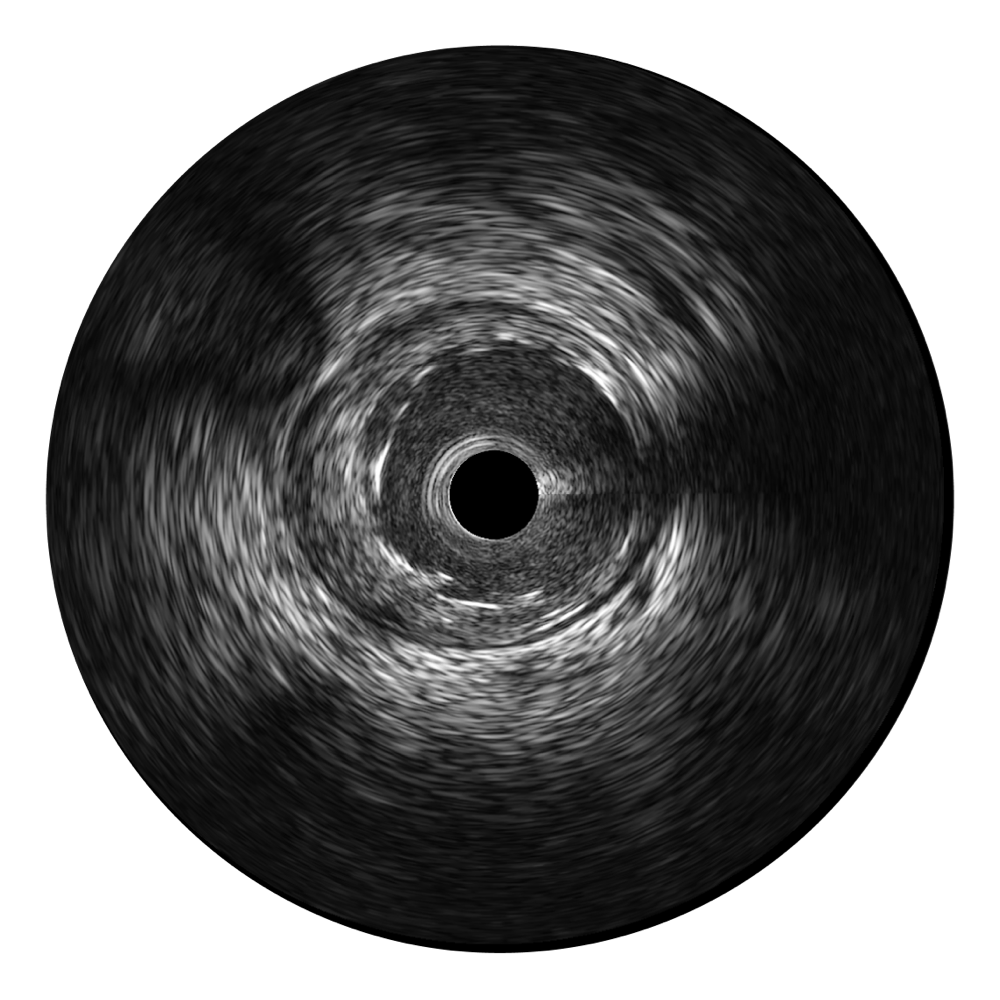

九州酷游超宽频成像技术覆盖20-80MHz1或20-90MHz2频率范围, 提供优异的分辨力同时也保证充足的穿透深度

对比传统IVUS导管成像,九州酷游宽频IVUS图像的近场支架梁显影更细腻,远场中膜外血管仍清晰可辨,兼顾远中近,兼顾分辨力与穿透深度